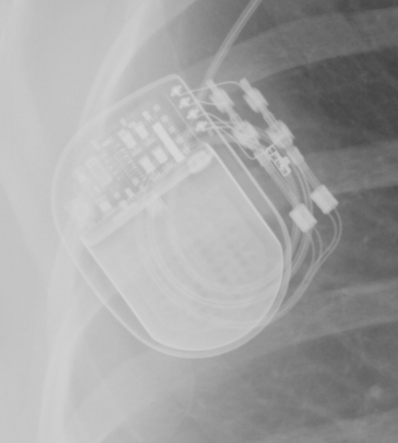

Röntgen Activa SC 37602 Neurostimulator

Röntgenbild eines implantierten Activa SC 37602 Neurostimulators der Firma Medtronic.